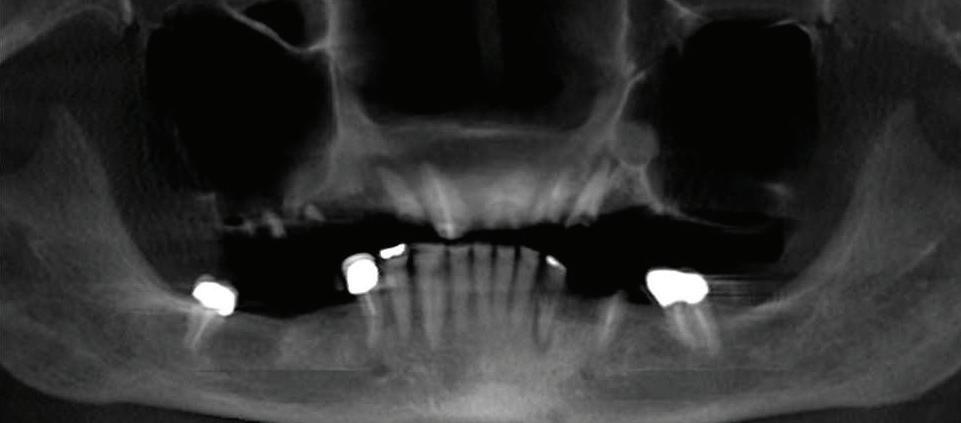

Submitted By Sivakumar Sreenivasan, DMD, MDS Dental Implant Center of Rockville

Can just four implants replace all of the teeth on the top or the bottom of your mouth? Thanks to advances in dental implant technology, that answer is a resounding yes.

Believe it or not, tooth loss is extremely common among adults, especially as we age. In fact, more than 35 million people in America are missing all of their upper and/or lower teeth. Rather than living with the discomfort and hassles of dentures, many people are opting for what is called “all-onfour” dental implant restoration.

All-On-Four:

One Full Arch Of Teeth, Four Dental Implants

To fully understand this remark-

A Reason To Smile Again All-On-Four

able technique for replacing teeth, you should first understand what a dental implant is. An implant is a small titanium screw that fits inside your jawbone and replaces the root-part of a missing tooth. Minor surgery is required to insert the implants. Once the implant is in place, a crown is attached to give you a highly realistic-looking and functional prosthetic tooth.

Here’s where it gets really interesting: You do not need a dental implant for each and every one of your missing teeth. All you need is four precisely placed implants on the top of your mouth, and four on the bottom, to restore your full smile. That’s the beauty of the all-on-four. And because the implant is made of titanium, it has the unique ability to fuse to living bone and function as part of it. So eventually, the dental implant becomes part of the jawbone and serves as a strong, long-lasting foundation for your new teeth.

What’s The All-On-Four Dental Implant Procedure Like?

It can be scary to get implants for the first time. Most of that fear is probably due to the uncertainty, so here is the step-by-step process for getting an All-On-Four dental implant.

First, your dentist will want to make sure your comfortable, so either local or general anesthesia will be administered.

Second, the dentist or surgeon will prepare your mouth for the implants, which involves removing your remaining teeth that are failing. They will then remove any diseased or infected tissue from your jaw and gums.

Besides ensuring that your implants are permanently fixed in place, this bone fusion has another important benefit: it prevents future bone loss in the jaw. This helps to maintain a more youthful facial structure – and better oral health. But perhaps the biggest surprise about the all-on-four is how quickly it can transform your life.

After the implants have been placed, they will thoroughly clean the surgical sites and suturing all the incisions. Then you’ll be taken to a recovery room where you can relax and take time to wake up from the anesthesia.

How Do You Know If The All-On-Four Procedure Is The Right Option For You?

At your All-On-Four consultation, you’ll receive a 3D CT Scan. This scan will help determine if you need implants and assist your doctors in creating your treatment plan. So if you want to learn more about dental implants, simply schedule a consultation with an All-On-Four provider. It’s the best way to find out how dental implants can change your life.

Next, they will begin the implantation process. This means they will insert the titanium screws into your jawbone. Most likely, they will place two implants toward the front of your mouth and two towards the back of your mouth so the “anchors” can evenly bare the force of the denture.

301-805-6805 16 | Your HEALTH Magazine All-On-4: Same Day Smiles CALL TODAY TO GET YOUR OLD SMILE BACK! 301.294.8700 Dental Implant Center of Rockville 77 South Washington Street, Suite #205 Rockville, MD 20850 • www.DrSreeni.com Courtesy 3D Planning For Implants When patients bring a 3D scan with them to or have one taken in the office. Appointment needs to be scheduled before May 15, 2024 Missing Teeth or Tired of Wearing Dentures? Thanks to advances in dental implant technology, just four implants can replace all of the teeth on the top or the bottom of your mouth.